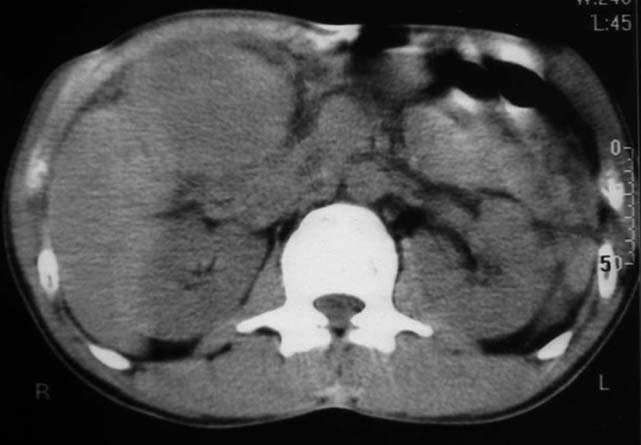

男,50y,右上腹包块痛10天,查:右上腹饱满,右肋下触及6*6cm大小包块,质硬,压痛。患者诉:10天前感冒胸闷,痛,后痛及右上腹部,既往有肝炎病史。

没有增强!只能考虑左叶内侧段巨块型肝癌(外生型)可能性大;胆囊呢?不除外胆囊癌累及肝脏。

病变位于胆囊窝内,其内密度不均,肝总管及胆总管扩张,胃里面没有清水充盈,不解为什么楼主不做好了准备再做呢,支持:“左叶内侧段巨块型肝癌(外生型)可能性大;不除外胆囊癌累及肝脏”建议增强吧。

首先考虑左叶内侧段巨块型肝癌(外生型),建议c+

我跟认为胆囊病变的可能性大,肠道准备不好,带来相关解剖结构的部位清晰。